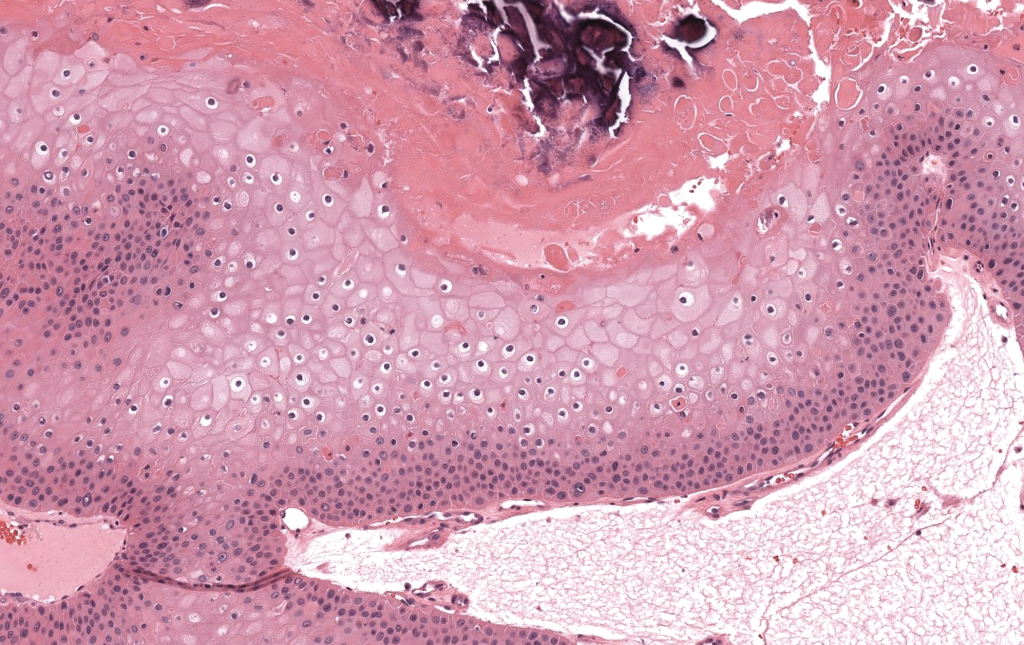

- Biopsia que muestre queratinización triquilemal y patrón lobulado-quístico. Folpe 2003.